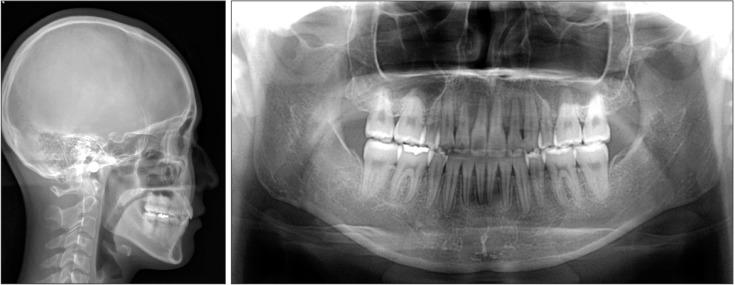

For patients with bimaxillary protrusion, significant retraction and intrusion of the anterior teeth are sometimes essential to improve the facial profile. However, severe root resorption of the maxillary incisors occasionally occurs after treatment because of various factors. For instance, it has been reported that approximation or invasion of the incisive canal by the anterior tooth roots during retraction may cause apical root damage. Thus, determination of the position of the maxillary incisors is key for orthodontic diagnosis and treatment planning in such cases. Cone-beam computed tomography (CBCT) may be useful for simulating the post-treatment position of the maxillary incisors and surrounding structures in order to ensure safe teeth movement. Here, we present a case of Class II malocclusion with bimaxillary protrusion, wherein apical root damage due to treatment was minimized by pretreatment evaluation of the anatomical structures and simulation of the maxillary central incisor movement using CBCT. Considerable retraction and intrusion of the maxillary incisors, which resulted in a significant improvement in the facial profile and smile, were achieved without severe root resorption. Our findings suggest that CBCT-based diagnosis and treatment simulation may facilitate safe and dynamic orthodontic tooth movement, particularly in patients requiring maximum anterior tooth retraction.

对于双颌前突患者,有时显著内收和压低前牙对于改善面部外形至关重要。然而,由于多种因素,治疗后上颌切牙偶尔会出现严重的牙根吸收。例如,有报道称,内收过程中前牙根尖接近或侵入切牙管可能会导致根尖牙根损伤。因此,确定上颌切牙的位置是此类病例正畸诊断和治疗计划的关键。锥形束计算机断层扫描(CBCT)可能有助于模拟上颌切牙及周围结构的治疗后位置,以确保牙齿安全移动。在此,我们展示一例双颌前突的安氏II类错牙合病例,其中通过对解剖结构的预处理评估和使用CBCT模拟上颌中切牙移动,将治疗引起的根尖牙根损伤降至最低。在没有严重牙根吸收的情况下,实现了上颌切牙的大量内收和压低,从而显著改善了面部外形和笑容。我们的研究结果表明,基于CBCT的诊断和治疗模拟可能有助于实现安全、动态的正畸牙齿移动,特别是在需要最大程度内收前牙的患者中。